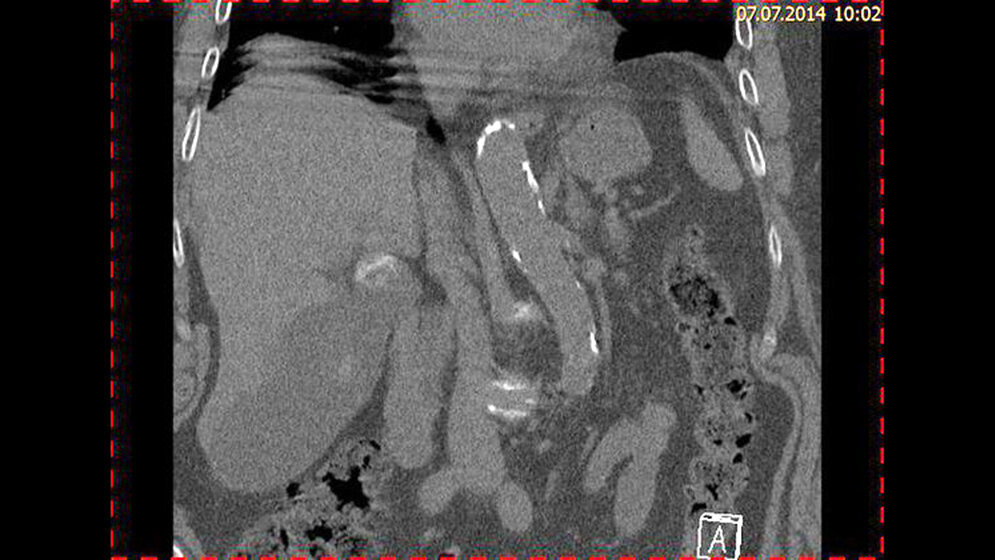

Zufallsbefunde: Cholezystolithiasis

Es gibt verschiedene Typen von Gallensteinen mit unterschiedlicher Mikrostruktur, Zusammensetzung und Verteilung. Gallensteine und Gallengangskonkremente kommen bei etwa 20 % der Bevölkerung vor. Die MR-Cholangiographie ist das derzeit beste nicht-invasive Verfahren zum Nachweis der Choledocholithiasis. Der Vergleich von MRCP, Ultraschall und CT zeigt die Überlegenheit der MRCP in der Beurteilung der Gallengänge und dem Nachweis von Steinen im Gal-lengang.